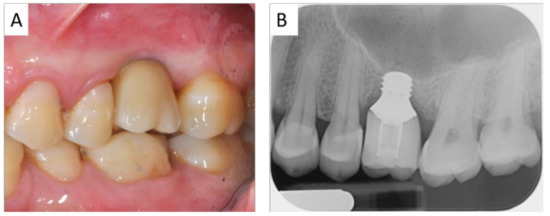

2.1. Planning

2.2. Surgical and Prosthetic Procedure